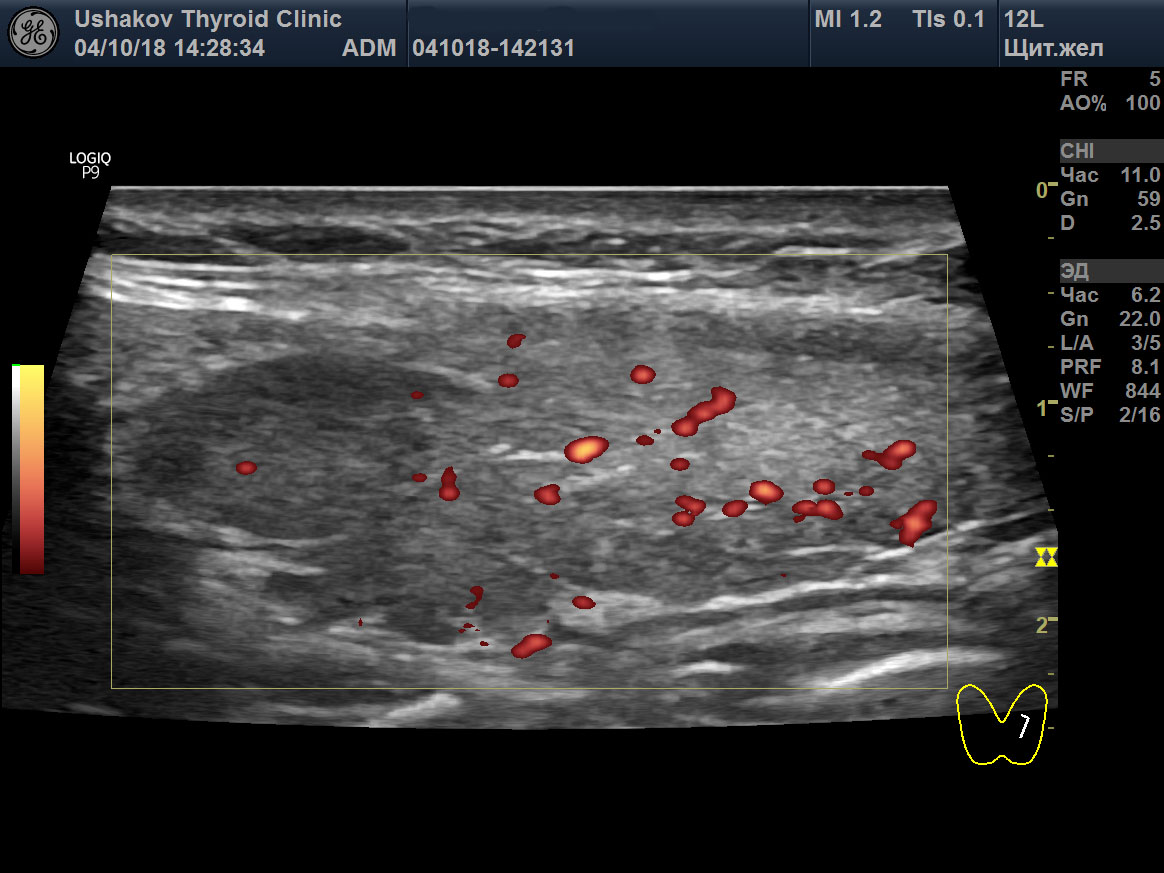

8. Сегменты щитовидной железы. Иммунный процесс в долях и перешейке ЩЖ часто протекает в пределах отдельных сегментов – малых (долек), средних (групп долек) и крупных, что определяется при УЗИ (

рис. 5). Обособленное развитие изменений (деструкция с последующей лимфоцитарной инфильтрацией и пролиферацией) в сегментах разных уровней – признак сегментарной нервной регуляции, способствующей обособленной (сегментарной) активизации перенапряжения и истощения тиреоидной ткани. Только локальное (в сегменте) изменение клеток ЩЖ ведёт к обособленной (сегментарной) активности иммунной системы – распознаванию и проникновению лимфоцитов в сегмент ЩЖ с изменённой тканью. Непосредственное нервное влияние на тиреоидные и иммунные процессы в отдельных сегментах ЩЖ реально и значительно достовернее, чем неподтверждённое и мало достоверное предположение об избирательной агрессии иммунной системы.

Рисунок 5 Левая доля ЩЖ пациентки 35 лет (продольная проекция; режимы В и ЭДК). В краниально-дорсальном крупном сегменте определяется умеренно гипоэхогенная ткань; в вентральном крупном сегменте – изоэхогенная ткань. Заметна чёткая граница между сегментами – гиперэхогенные тяжи соединительнотканной природы. В изоэхогенной зоне интенсивность кровотока в малой степени усилена, в гипоэхогенной – ослаблена (из-за истощения ткани).